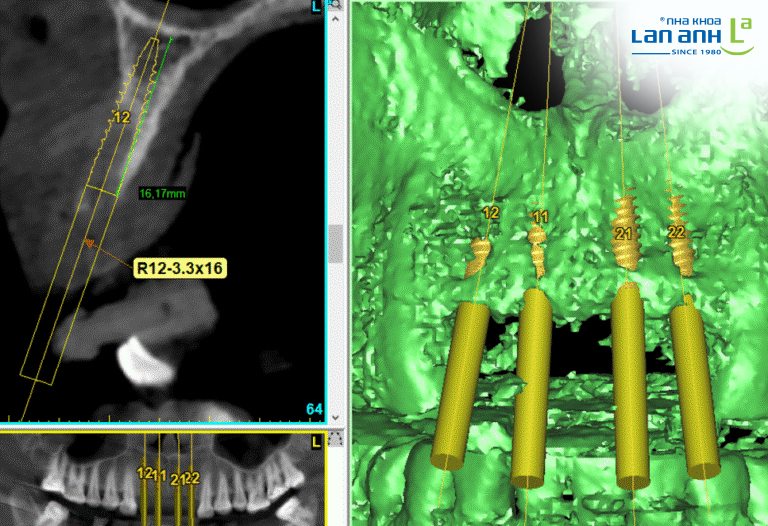

Nếu như x-quang toàn cảnh chỉ cho hình ảnh 2 chiều gần - xa thì phim Cone beam 3D cho thấy cả mặt ngoài - trong. Như vậy việc xác định độ dày của xương hàm sẽ chính xác hơn.

Khi cấy ghép implant, bác sĩ chắc chắn sẽ cần phim toàn cảnh. Tuy nhiên, với những trường hợp xương hàm mỏng, khám lâm sàng và phim x-quang toàn cảnh không đủ để phán đoán chính xác có thể cấy ghép implant được không. Vậy nên việc yêu cầu chụp phim Cone beam 3D là hết sức cần thiết.

Ngoài việc xác định bề dày của xương hàm để quyết định đường kính implant phù hợp, phim Cone beam 3D còn cho thấy vị trí dây thần kinh hàm dưới, vị trí xoang hàm trên (để hạn chế tối đa rủi ro cấy ghép không thành công).

Phim CT Cone beam cho thấy bề rộng của xương có đặt implant được không